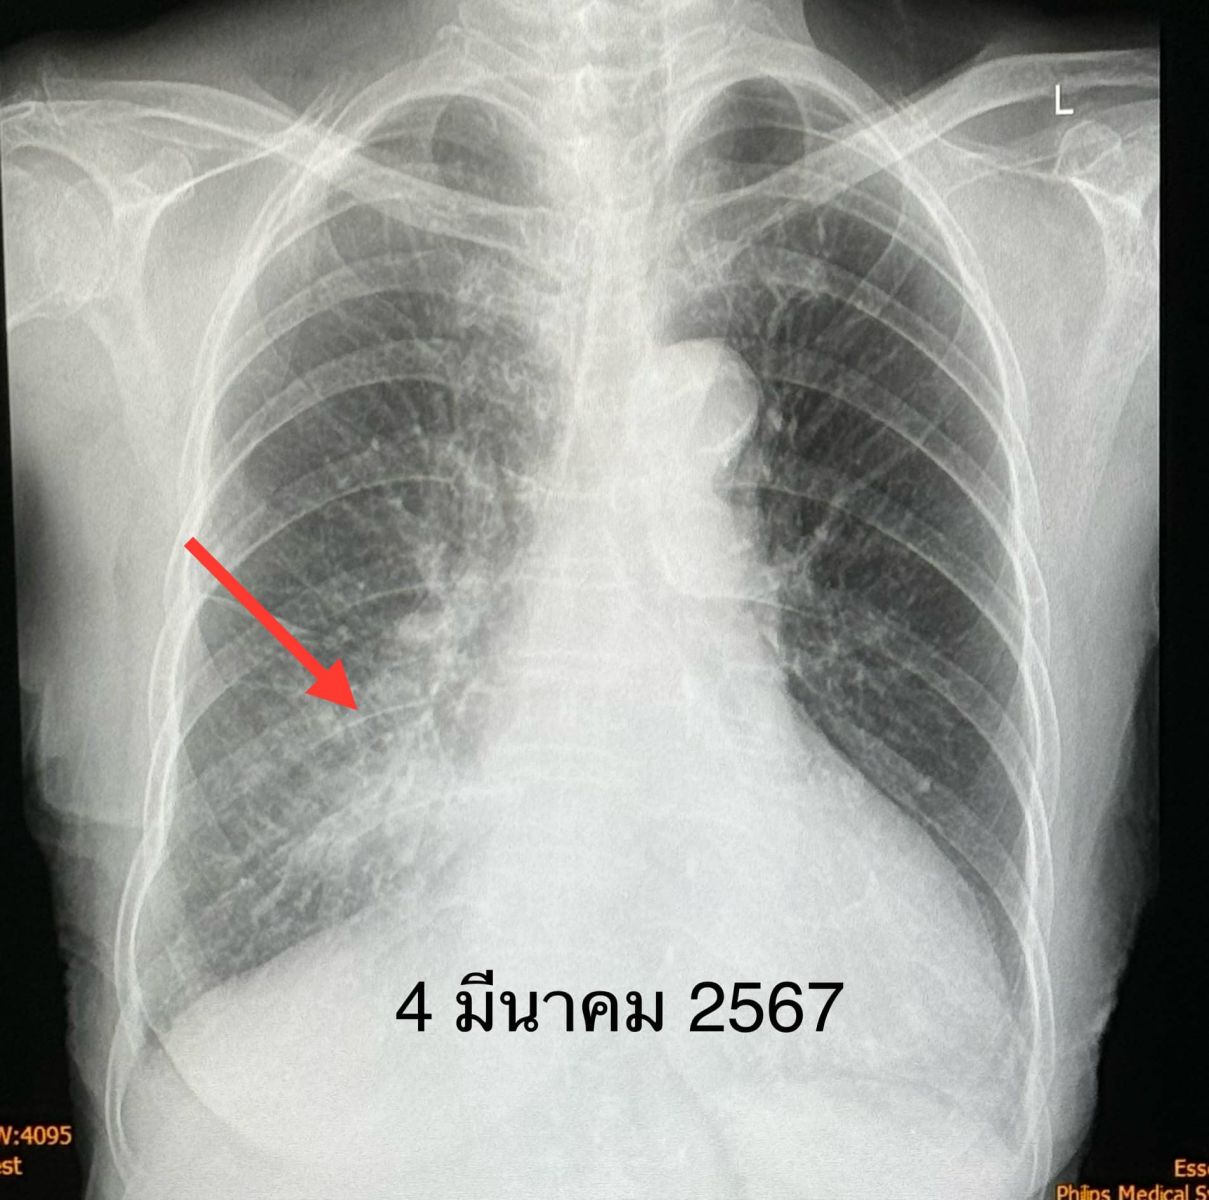

ตรวจร่างกาย อุณหภูมิ 38 องศาเซลเซียส ระดับออกซิเจนปกติ 96% ฟังปอดปกติ ส่งตรวจรหัสพันธุกรรม 22 สายพันธุ์ พบเชื้อไรโนไวรัส (Rhinovirus) เพียงตัวเดียวเอกซเรย์ปอดพบฝ้าขาวที่ปอดด้านขวาล่าง (รูปวันที่ 4 มี.ค.2567) เจาะเลือด เม็ดเลือดขาวปกติ ส่งเพาะเชื้อในเลือดไม่ขึ้นเชื้อแบคทีเรีย

วินิจฉัย : ปอดอักเสบจากเชื้อไรโนไวรัส (Rhinovirus) ให้ยาสเตียรอยด์ขนาดต่ำๆ 5 วัน ผู้ป่วยดีขึ้น ไม่มีน้ำมูก ไม่เจ็บคอ ไม่มีไข้ ไอลดลง เอกซเรย์ปอดฝ้าขาวลดลง (รูปวันที่ 8 มี.ค.2567) นอนในโรงพยาบาลทั้งหมด 5 วัน ติดตามหลังจากออกจากรพ. 5 วัน ไอน้อยลงมาก เอกซเรย์ปอดฝ้าขาวด้านขวาล่างลดลงอีก (รูปวันที่ 13 มี.ค.2567)